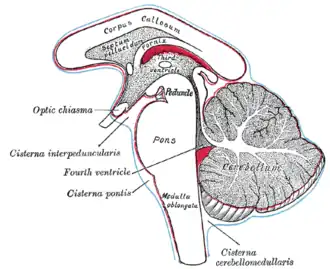

Diagram showing the positions of the three principal subarachnoid cisterns. (Lateral recess not labeled, but region is visible.) | |

The lateral recess or lateral recess of fourth ventricle, is a projection of the fourth ventricle which extends to the lateral border of the brainstem at the pontomedullary junction.[1][2] At this point the fourth ventricle is at its widest.[1]

The lateral recess on each side opens into a lateral aperture (foramen of Luschka) that opens into the subarachnoid space at the cerebellopontine angle. This provides a pathway for the ventricle's cerebrospinal fluid into the subarachnoid space.[1]